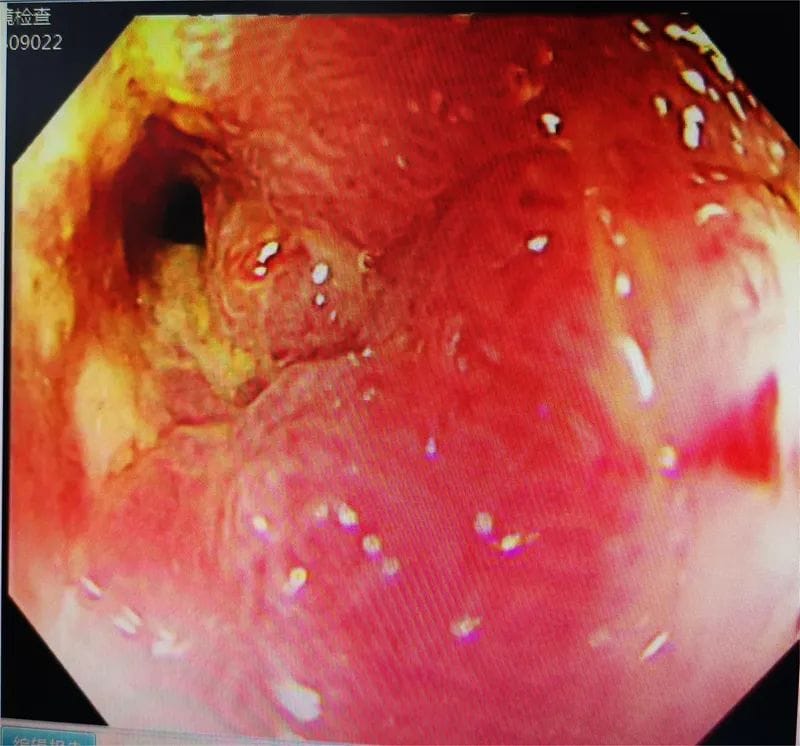

3月11日下午,邀请重庆医科大学第一附属医院文光旭教授作技术指导,在麻醉与围术期医学科和介入科的积极配合下,郭军博士带领团队利用C臂引导结肠造影为患者进行手术。医生在内镜下通过一根引导导丝将支架放到梗阻部位,并运用网状支架将肠道撑开,在堵塞的肠腔中撑开一条通道,形成真正意义上的“疏导”,为患者打通“生命通道”,手术顺利完成。

患者,老年男性,腹痛、腹胀、排便困难长达数月之久,近日因病情加重转诊至我院,来时患者呕吐隔夜宿食,腹胀如鼓,入院后,经各项检查初步诊断为横结肠肿瘤并胃、十二指肠及胆胰管、胰头及邻近腹膜组织、周围淋巴结转移,伴近端肠管梗阻扩张。消化内科主任医师郭军博士带领团队对病例进行评估,考虑到患者为恶性肿瘤晚期,全身状态欠佳,而置入肠道支架对患者来说创伤小、并发症少,病人痛苦小,恢复快,无疑是更优的选择。但该病患梗阻部位特殊,即横结肠近肝曲,该部位迂曲且薄弱,且肠道狭窄处仅约0.3-0.4mm大小,支架置入困难,有出血、穿孔、置入失败等风险。医生向患者及家属交代病情及风险后,家属果断选择内镜下结肠支架置入术。该手术是采用金属支架作为肠腔内支撑治疗结直肠恶性梗阻,对于患者来说就像做了一次胃肠镜检查。